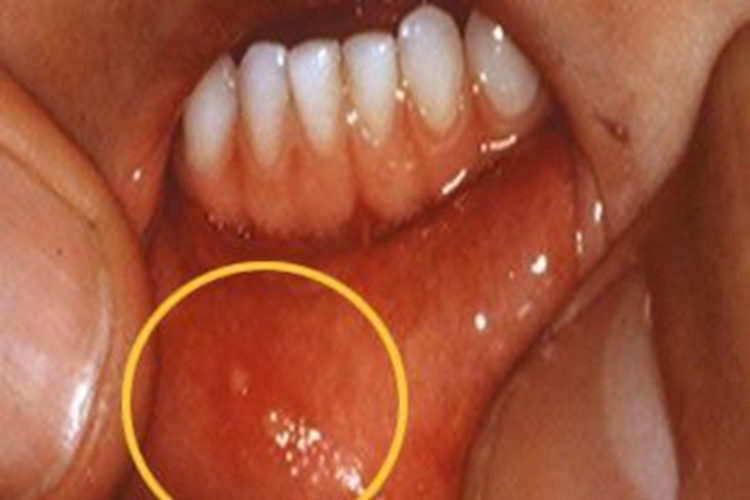

手足口病可累及唇内侧,可表现为唇内侧有许多密集的小水疱,呈白色的小点样,周围伴有红晕,患者自觉疼痛。